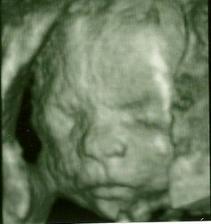

Naše druhé :o)